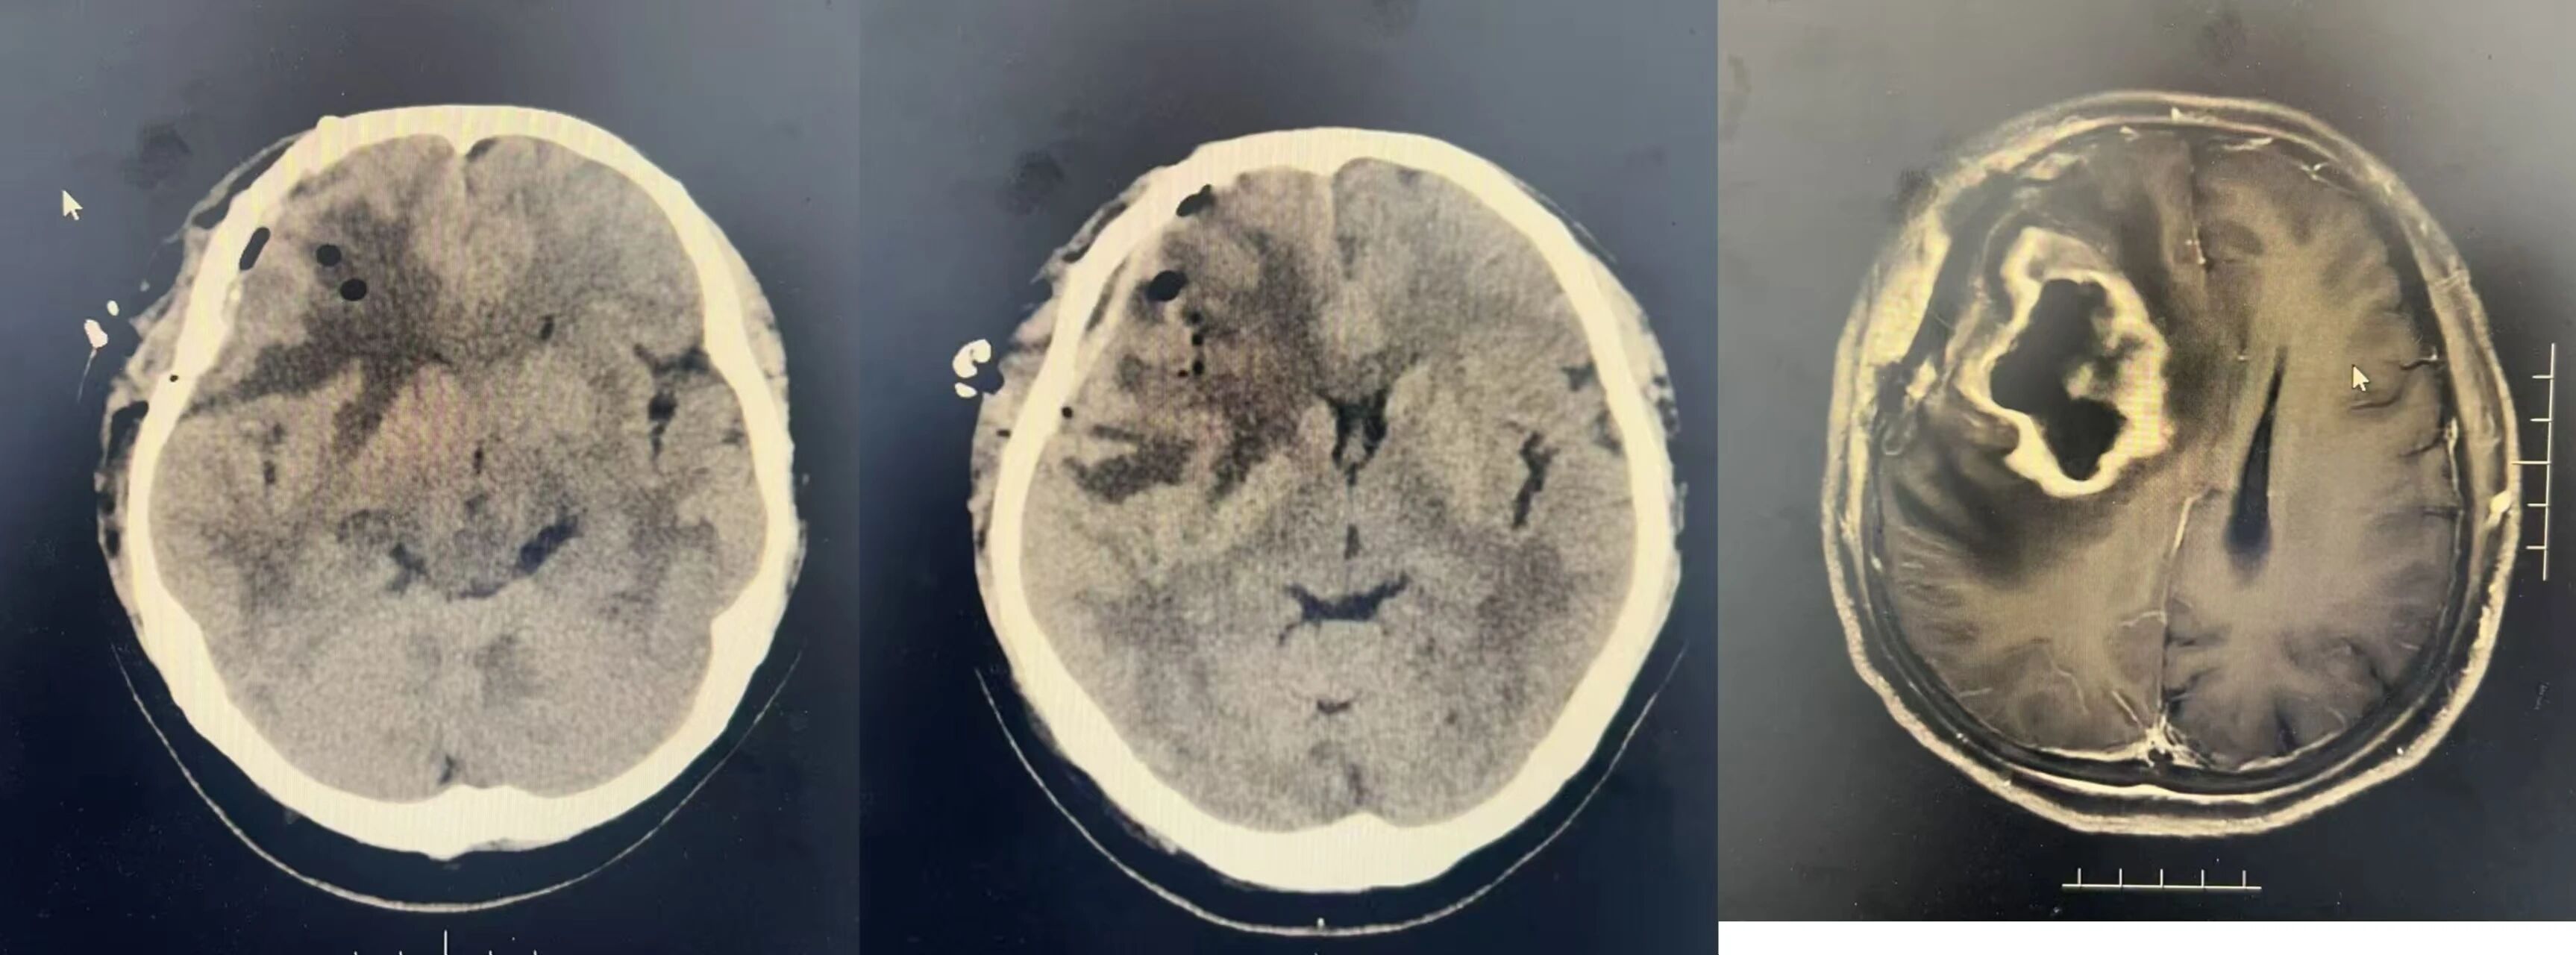

经过周密的术前准备后手术得以顺利实施,术中过程顺利,肿瘤镜下完全切除,术后未出现手术副损伤症状以及围手术期并发症,病人术后恢复情况良好,术后病理提示黑色素瘤。病人家属对手术效果非常满意。

术后